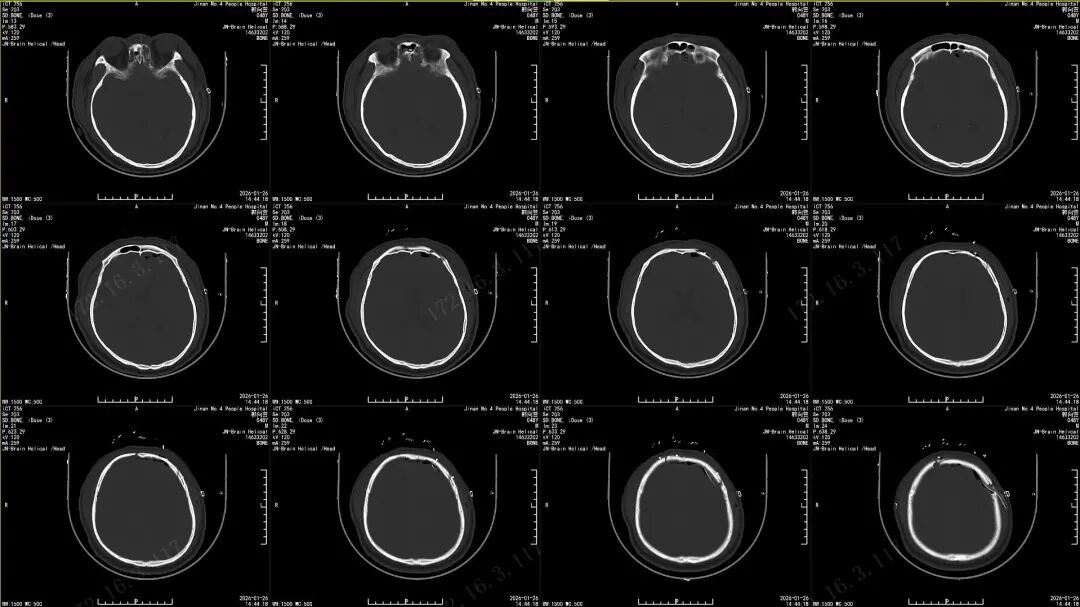

近日,济南市第四人民医院神经外二科接诊了一位特殊患者。这位中年男性因意外被金属异物击穿鼻腔,经左侧眼眶刺入大脑,来院时前额与鼻腔流血,双眼青紫肿胀,情况危急。头颅CT显示:异物已穿过眶内上壁进入颅内,位置深且紧邻重要血管与神经,手术风险极高——稍有不慎就可能引发大出血或神经功能损伤。

时间就是生命。科室立即启动急诊创伤救治预案,由济南市第四人民医院神经外二科滕宏涛主任牵头成立救治小组。通过三维重建CT,团队精准规划了手术入路,并制定了涵盖神经血管保护、异物取出与前颅底修补重建的个性化手术方案。

术前、术中影像